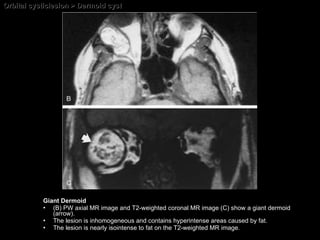

Orbital cysticlesion > Dermoid cyst Giant Dermoid (B) PW axial MR image and T2-weighted coronal MR image (C) show a giant dermoid (arrow).  The lesion is inhomogeneous and contains hyperintense areas caused by fat.  The lesion is nearly isointense to fat on the T2-weighted MR image.